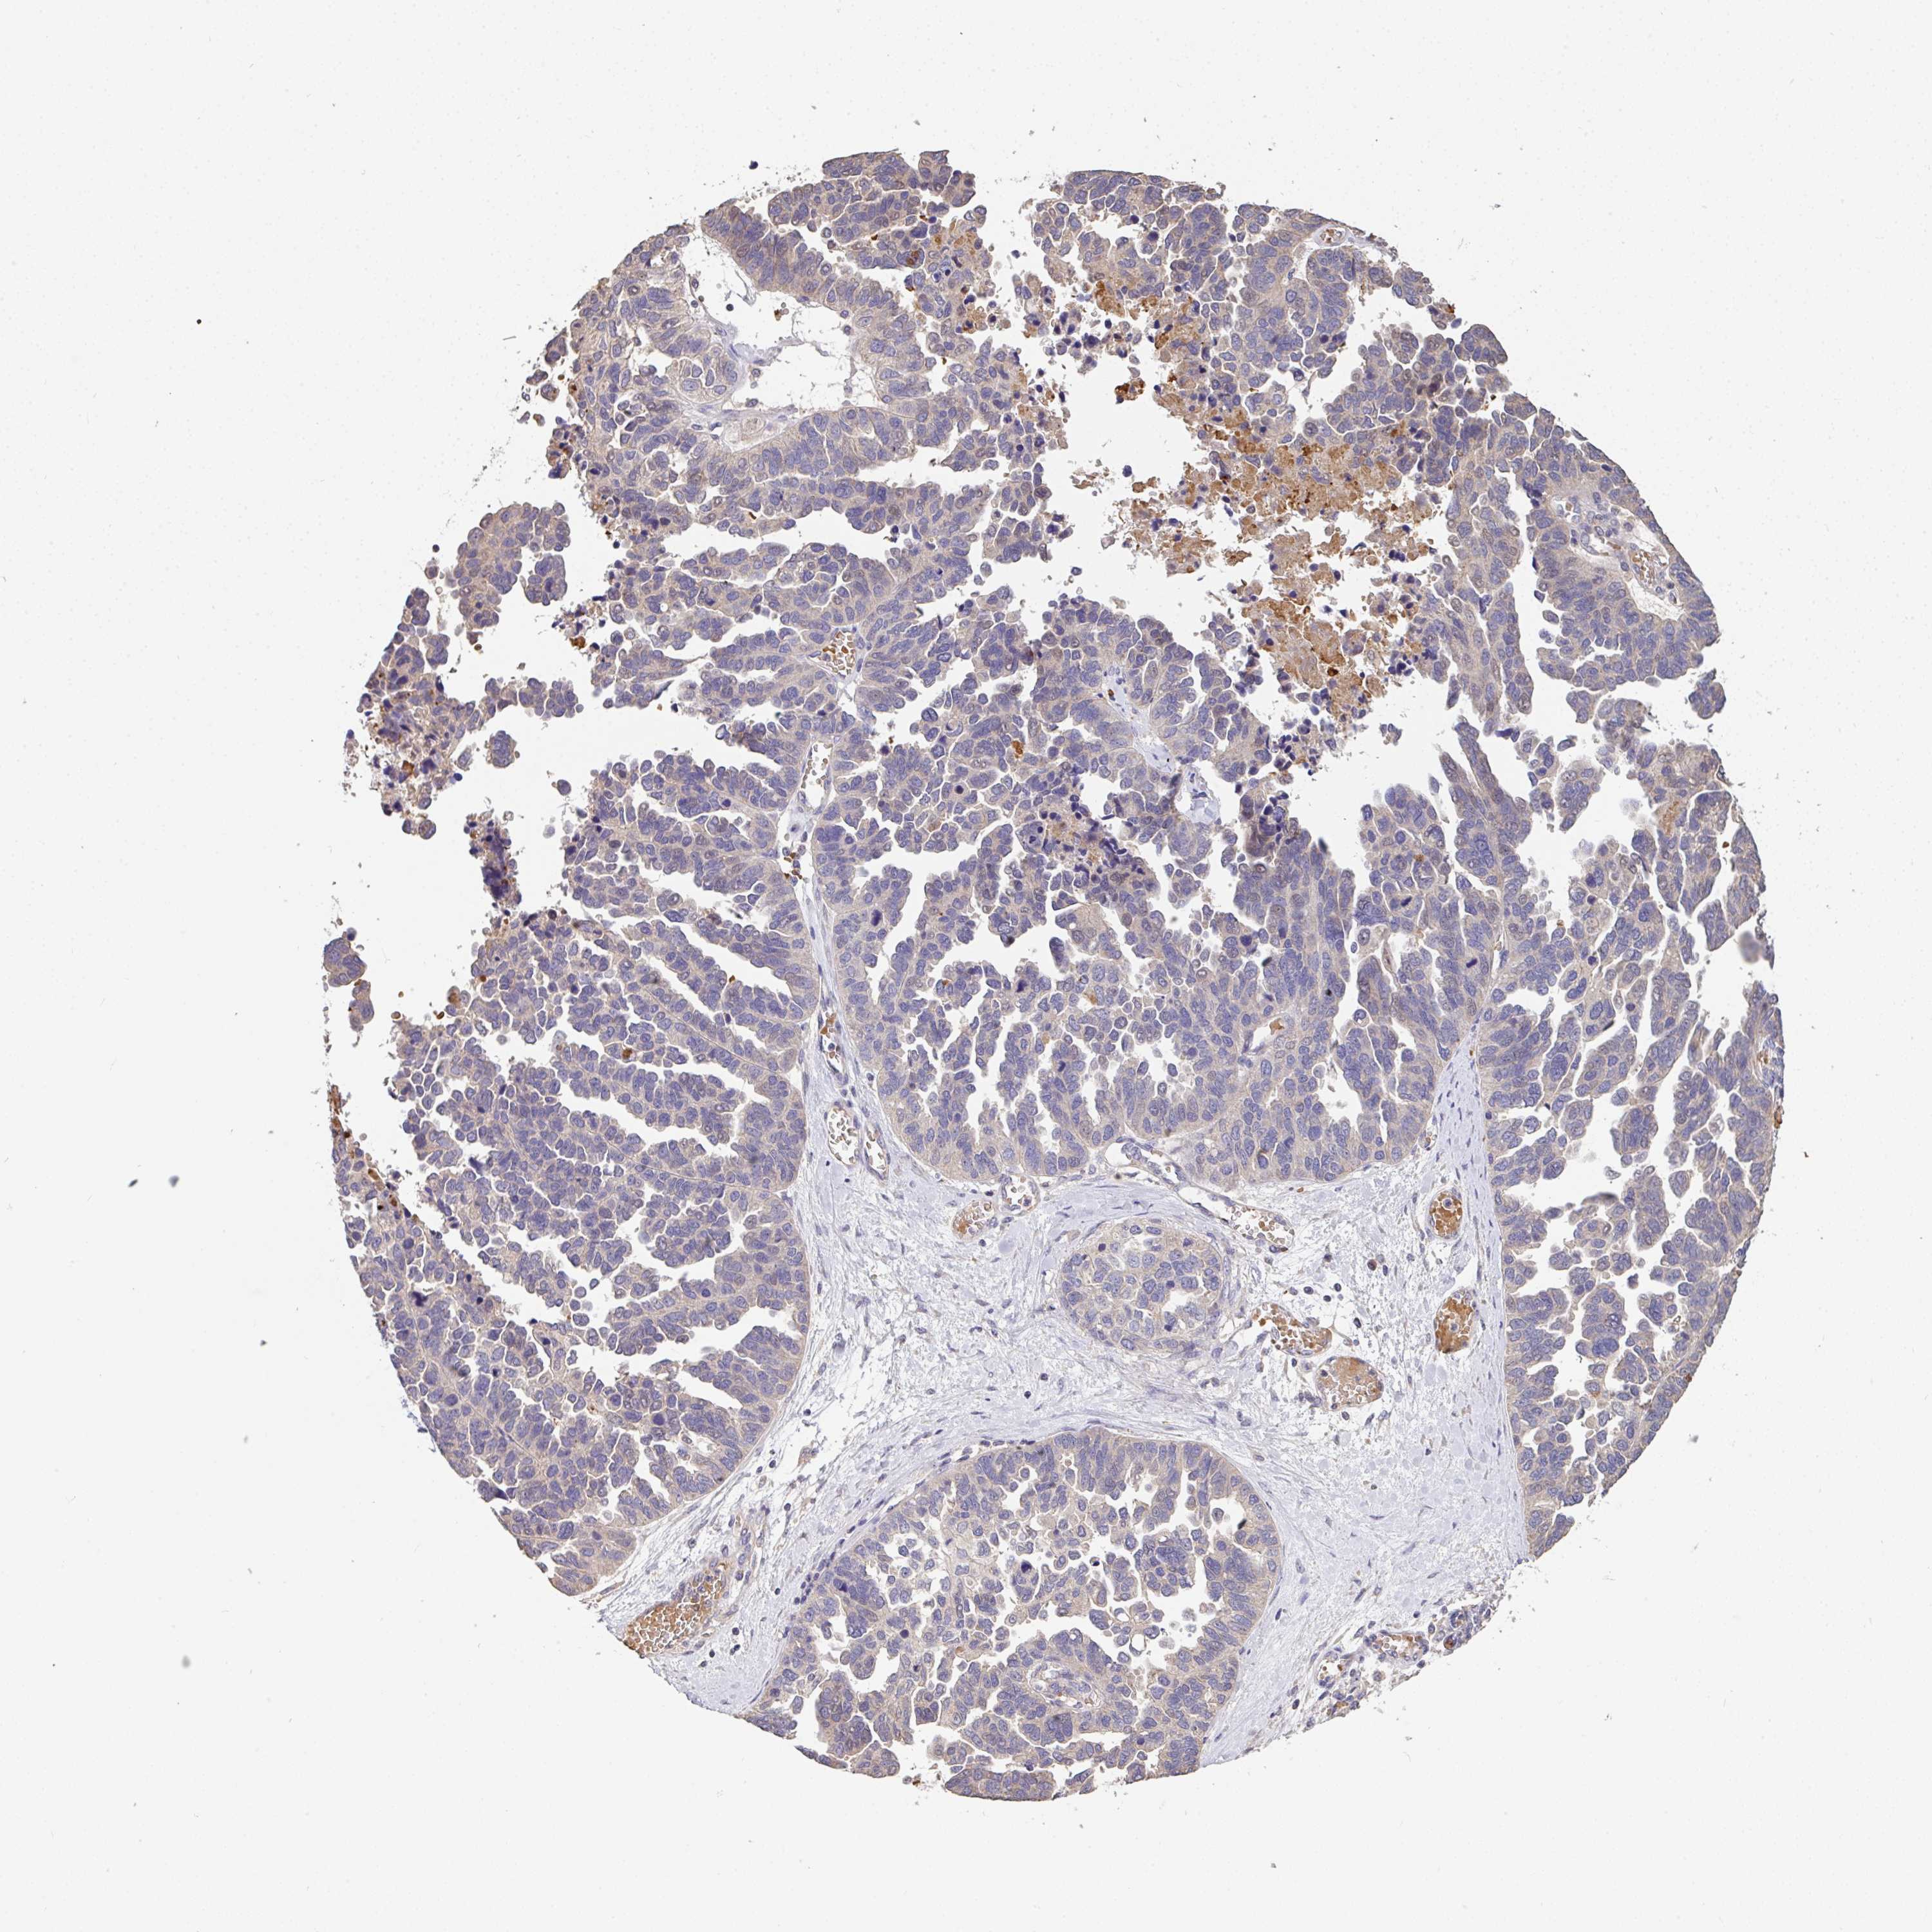

OVARIAN CANCER - Protein expressioni

A mouse-over function shows sample information and annotation data. Click on an image to view it in a full screen mode. Samples can be filtered based on level of antibody staining by selecting one or several of the following categories: high, medium, low and not detected. The assay and annotation is described here.

Note that samples used for immunohistochemistry by the Human Protein Atlas do not correspond to samples in the TCGA dataset.

Antibody stainingi

Antibody staining in the annotated cell types in the current human tissue is reported as not detected, low, medium, or high, based on conventional immunohistochemistry profiling in selected tissues. This score is based on the combination of the staining intensity and fraction of stained cells.

Each image is clickable and will lead to virtual microscopy that enables deeper exploration of all samples and also displays staining intensity scores, fraction scores and subcellular localization as well as patient and tissue information for each sample.

Antibody HPA056632

Cystadenocarcinoma, serous, NOS

Cystadenocarcinoma, mucinous, NOS

Carcinoma, endometroid